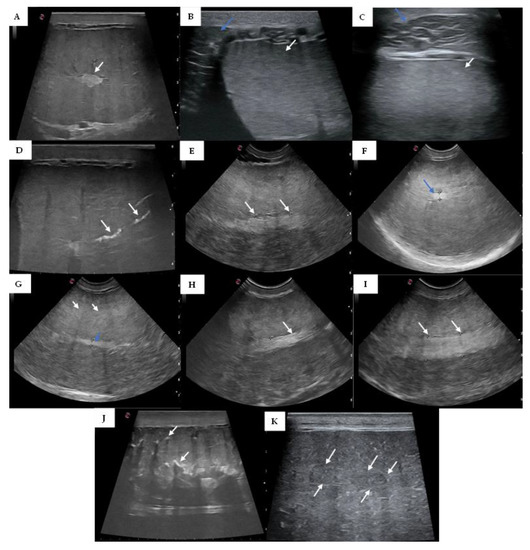

3.1. Testicular Ultrasonography